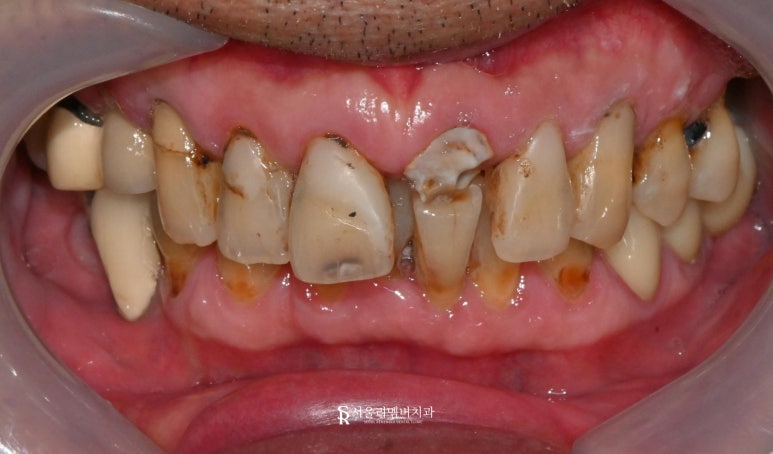

초진

"선생님, 앞니가 깨지고 충치가 많아요.

민망해서 웃을 수가 없어요."

환자께서는 위에 앞니가 깨지고

거뭇거뭇해 미소를 잃었다고 하셨습니다.

일단 구강 카메라로 찍은 사진 한번 보겠습니다.

사진을 보니

구강 전체가 관리가 안 된 걸 볼 수 있습니다.

그리고 심하게 깨진 위쪽 앞니가 보이는데요.

많은 부분이 깨져나가 심한 통증도

동반하고 계셨습니다.